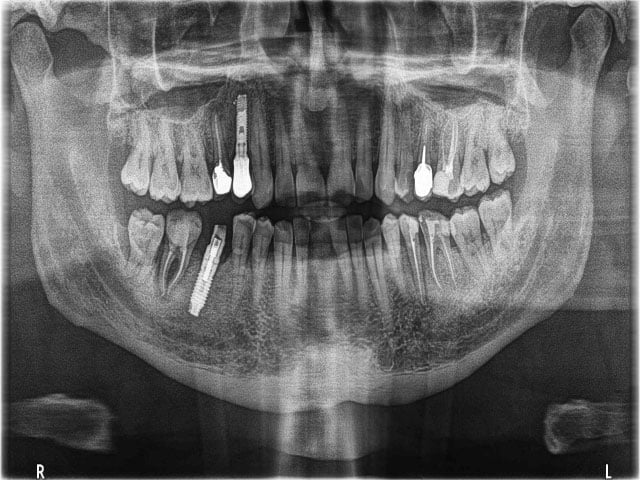

Panoramik ve sefalometrik röntgenler, ağız içi ısırma röntgenleri tarafından kaçırılan burun ve sinüs geçişlerini gösterir. Sefalometrik X-ışınları genellikle panoramik bir röntgen cihazı ile çekilir. Uyarlanmış makinenin mekanik bir kol üzerine monte edilmiş özel bir sefalometrik film tutucusu olacaktır. Diş hekimine tüm ağız yapısının resimlerini sağlamak için bir X-ışını görüntü reseptörü iyonlaştırıcı radyasyona maruz bırakılır. Hem sefalometrik hem de panoramik röntgenlerin avantajı, vücudun daha az radyasyona maruz kalmasıdır.

Ortodontik planlamaya yardımcı olur. Filmlerde sefalometrik X-ışınları tamamen ağrısızdır. Kafa, mekanik döner kol ile başka bir kol üzerine yerleştirilen film tutucu arasına yerleştirilir. Kol başın etrafında dönerek yüz, ağız ve dişlerin görüntülerini yakalar. Görüntülerin netliği ve keskinliği vücudun konumuna bağlı olacaktır. Görüntüler genellikle%30’a kadar büyütülür, bu nedenle herhangi bir çürüme, hastalık veya yaralanma belirtisi görülebilir ve tedavi edilebilir.

Röntgen çektikten sonra, diş hekimi başın tam bir yan profilini görebilecek. Bu, ortodontik planlamaya yardımcı olabilir ve diş tellerinin yüz profilini ve dişleri nasıl etkileyebileceğinin anında değerlendirilmesine olanak tanır. X-ışını için başka bir yaygın kullanım, diş implantlarının oluşturulması ve yerleştirilmesinden önce belirli ölçümleri belirlemektir. Sefalometrik röntgenler hakkında herhangi bir sorunuz veya endişeniz varsa, lütfen diş hekiminize sorun.